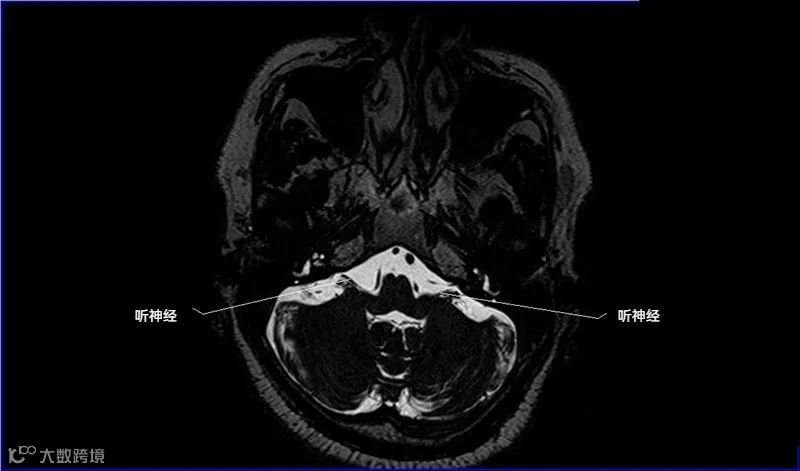

十二对脑神经口诀

一嗅二视三动眼,四滑五叉六外展,

七面八听九舌咽,迷走及副舌下全。